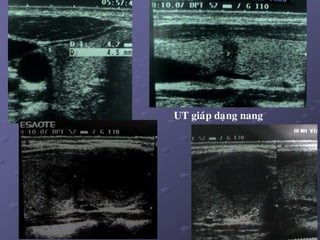

2/. Nhaân giaùp daïng nang:

a. Ñaëc tính:

 Nang giaùp thaät söï ít thaáy.

 Phaàn lôùn nang giaùp thöôøng gaëp laø nang keo do keát tuï

dòch keo trong caùc tuùi nang, dòch vaøng, seät. Khi coù xuaát

huyeát = nang giaû maùu (pseudo – heùmatique).

b. Hình aûnh SA: ña daïng, tuøy theo giai ñoaïn (tuoåi cuûa nhaân).

Löu yù: K gíap khoâng bao giôø bieåu hieän döôùi daïng nang hoøan toaøn.